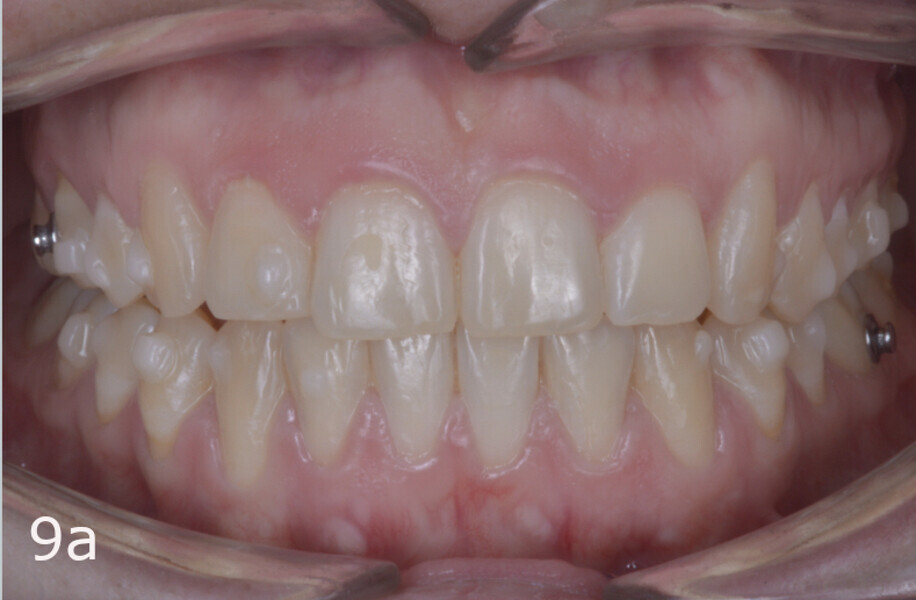

The treatment objectives included closing the anterior open bite, achieving a bilateral Angle Class I relationship and a proper overjet and overbite, correcting the midline discrepancies, and achieving a profile harmonisation. The treatment plan consisted of orthodontic camouflage treatment with asymmetric distalisation in three of the four quadrants using Invisalign aligners (Align Technology) and third molar extraction. The Invisalign Comprehensive package was chosen, and 63 pairs of aligners were used (Figs. 7–10). Each aligner was worn for 20 hours a day for one week each. The use of Class III elastics on both sides was indicated. Afterwards, ten refinement aligners were needed to improve the interdigitation on the right side (Figs. 11 & 12).